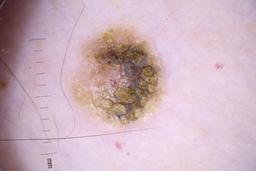

- Name: Challenge 2020: Training

- Number of images: 33,126

- Number of specified lesions: 32,701

- Number of specified patients: 2,056